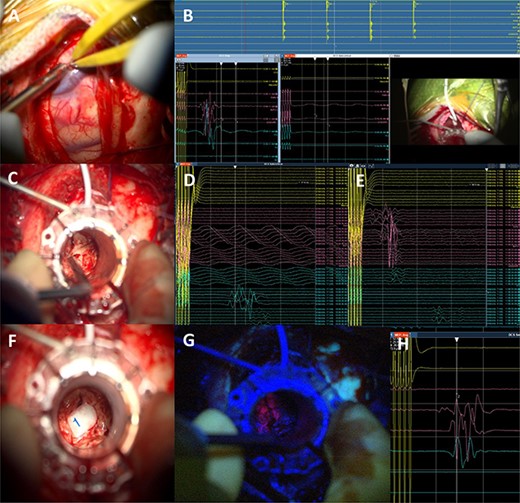

Intraoperative technical illustration: (A) transsulcal approach; (B) subdural strip of electrodes placed under preoperative nTMS and DTI guidance with stable responses at 7 mA; (C) docking of the BrainPath tubular retractor with positive responses of the anterior tibialis at 17 mA during the cannulation of the brain, insertion stopped at this point; (D) stimulation through the tube identified motor responses at 17 mA from lower limb muscles (tibialis anterior and abductor hallucis); (E) direct subcortical stimulation identified motor responses from upper and lower limb muscles at 7 mA; (F and G) Tumour subtotal resection stopped at 5 mA for the upper limb and 7 mA for the whole CST. The tumour demonstrated 5-ALA-induced fluorescence under the BLUE 400 filter; (H) activity from hand muscles at 5 mA threshold during removal of BrainPath tubular retractor before closure.

5-Aminolevulinic Acid (5-ALA) was given orally 2 h before the surgery. The least disruptive trajectory was selected taking into account the previous biopsy and the preoperative mapping information (Fig. 3). Under Stealth guidance, a skin incision was made overlying the planned craniotomy site. After the craniotomy, the dura was opened and a subdural strip of electrodes was placed over the primary motor cortex. Replicable motor responses from the hand muscles were obtained at 7 mA current intensity (Fig. 4). Motor evoked potentials (MEPs) were obtained continuously throughout the procedure. A transsulcal parafascicular approach was used. The sulcus was opened sharply under the microscope. At the depth of the sulcus, a preselected tubular retractor (NICO BrainPath 75 mm × 13 mm) was passed to the superficial surface of the lesion. While performing brain cannulation to the lesion, a monopolar probe (INOMED©) navigated with SureTrack (MEDTRONIC©) was used to perform continuous subcortical stimulation, train-of-five technique using high-frequency stimulation.

Once the superficial aspect of the lesion was reached, positive stimulation of the lower limb was identified at 17 mA (Fig. 4). The tubular retractor was fixed with a Leyla retractor system and held manually to prevent displacement. Multiple tissue samples were obtained from 5-ALA-induced fluorescent tissue. Intraoperative smear was consistent with high-grade lesion. After the biopsy was performed the tubular retractor was slowly removed. Using a monopolar probe for subcortical stimulation directly through the surgical site, we were able to confirm the proximity to the CST at 5 mA to the lower limb motor fibres. Cortical MEPs were stable during the whole procedure.